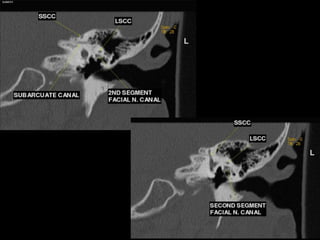

 Semicircular canals (SCC), superior (S), lateral (L) &. posterior (1')

SSCC: Projects cephalad; bony ridge over SSCC in roof of petrous

pyramid called arcuate eminence

LSCC: Projects into middle ear with tympanic CN7 on under side

PSCC: Projects posteriorly parallel to petrous ridge

 Intratemporal facial nerv;

CN7 segments: lAC, labyrinthine, tympanic, mastoid segments

Geniculate ganglion = anterior genu

Posterior genu: Tympanic segment bends inferiorly to become mastoid

segment